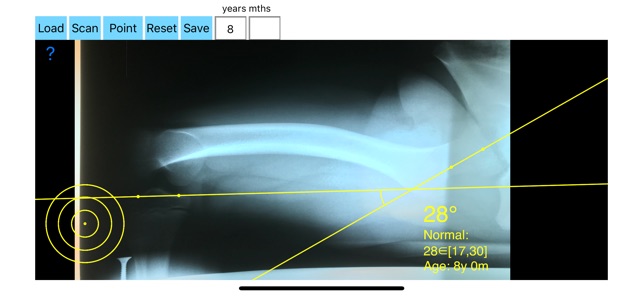

Femoral anteversion is defined by the angle of the femoral neck in relation to the femoral shaft in the coronal plane. Femoral rotational malalignment is associated with pain and functional disability, hip impingement and instability. Measurement of anteversion of the femoral neck is an important component of surgical planning, for femoral osteotomy in patients with cerebral palsy or developmental dysplasia of the hip and total hip replacement surgery. In-toeing gait due to excessive femoral anteversion is common entity in outpatient children clinics.The in-toeining is usually resolved spontaneously but there are children after 8 years of age that the in-toeing fails to correct spontaneously and objective monitoring is important. Normal values according to patients age especially in clinical settings are hard to be remembered. Monitoring of Femoral Antetorsion is indicated especially in cases with torsional malalignment syndromes and cerebral palsy .

Numerous studies on the measurement of femoral torsion have been published with different method. The amount of anteversion of the hip usually is measured with computed tomography (CT) scan. The modified Budin view (posteroanterior hip radiograph obtained in the sitting position with the patient facing the film in 90° flexion of the hip and knee with the hip abducted by 30° ) offers a way to measure anteversion by simple x ray without the use of CT and thus reducing radiation exposure and patient cost.

-By marking few points at the image of X-ray, the App calculates and offers a very convenient way to determine the most accurate possibly way at once.

-Save the planned images, for later review or consultation.The measured values are compared by normal reference databases according to age of the patient and help decide what are pathologic or normal.

In a busy everyday practice, the examiner have to draw lines in X-rays or in clinical settings, this it is time consuming and cumbersome. Accessory instruments like protractors, hinged goniometers, well sharped pencils, rulers or even transparent papers must be available. The app offers a very convenient and accurate way to perform most common radiographic measurements in a blink of an eye in front of your screen. The build in feature of the app, allows results to be categorized ( increased anterversion, excessive anteversion, decreased anteversion, or retroversion) according patient’s age by comparing the data with normal reference database, this feature may help decide what could be considered normal or pathologic.